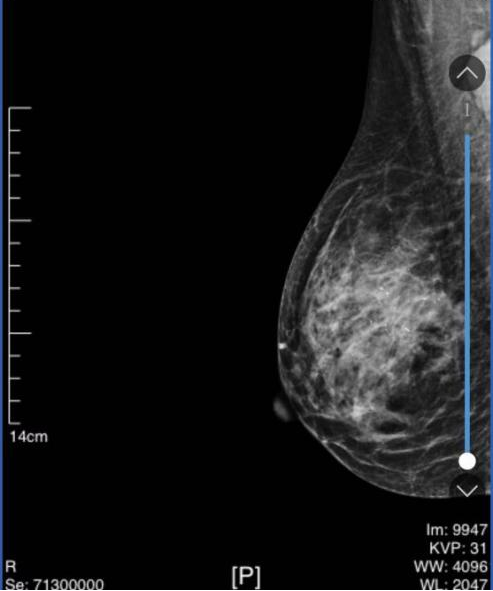

• 乳腺钼

靶

1、双侧乳腺实质呈不均匀致密型。

2、右乳外上象限可见稍高密度肿块(断层所示CC位22/66、MLO位12/68),边缘分叶,大小约27mm*21mm。右乳外上象限可见多发细小多形性钙化灶。局部呈簇状分布。右乳中外象限似可见稍高密度小肿块(断层所示CC位33/66、MLO位21/68),长径约6mm。

钼靶提示:右乳外上象限肿块伴微钙化,右乳外上象限成簇状钙化灶,BI-RADS 4C类

图2 乳腺DR结果(2024-02-29)